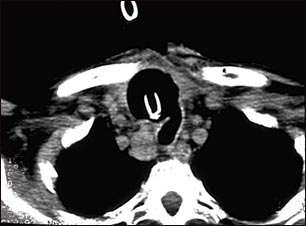

Tomografía computarizada de cáncer de tiroides

TC de la parte superior del tórax que muestra un tumor maligno (cáncer) tiroideo. Se ha producido la destrucción y muerte (necrosis) del tejido normal en el área oscura alrededor de la tráquea (marcada por la punta blanca en forma de U del tubo respiratorio), como resultado del crecimiento del tumor.